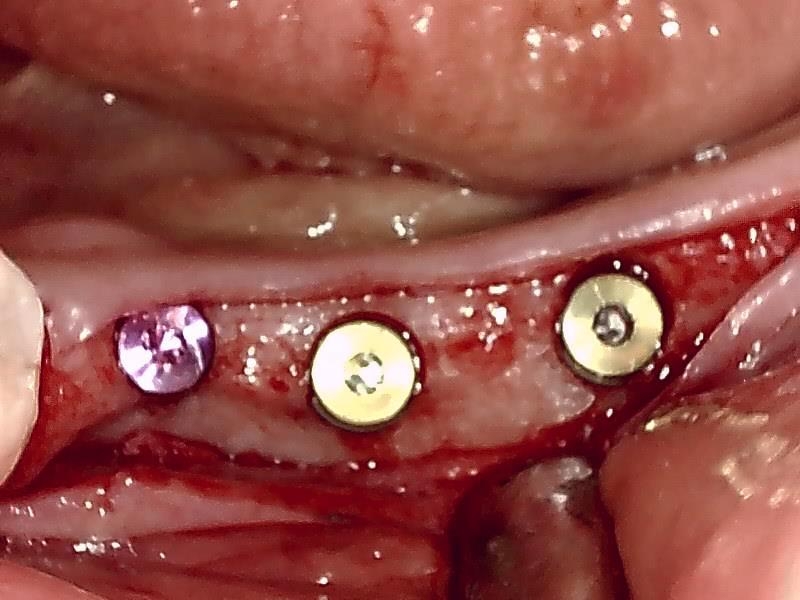

術中インプラント埋入した状態は良好です。

自家骨移植 GBR を施す。理想的な顎堤に築造する。